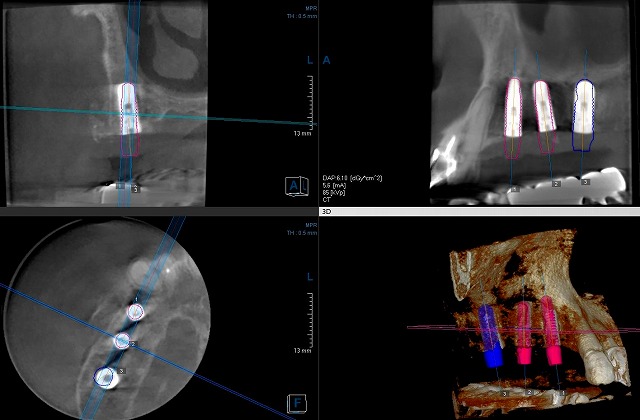

インプラントオペ

昨日東京から帰ってすぐに月曜日の朝からインプラントの手術でした。今日のオペは難しくはなく、骨の幅も高さも有り楽勝のような感じが有りました。もともとは歯を抜いて10年近く経っていて骨そのものは吸収して高さが下がっていました。しかし元々がもっと厚い骨が有ったのでしょうね。ソケットリフトやサイナスリフトをする必要もなくすんなりと終わる予定でした。